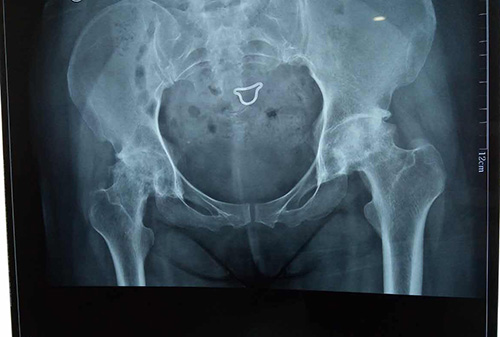

股骨头坏死,又称股骨头缺血性坏死,为常见的骨关节病之一。大多因激素、酒精、外伤等因素,及风湿病、血液病、潜水病、烧伤等疾患引起,先破坏邻近关节面组织的血液供应,进而造成坏死。其主要症状,从间断性疼痛逐渐发展到持续性疼痛,再由疼痛引发肌肉痉挛、关节活动受到限制,最后造成严重致残而跛行。 ◎真实的分享,融通血管助您恢复健康 —经诊断为双侧缺血性坏死,右侧甚— 2015年10月,刘女士感觉髋关节疼痛,在当地医确诊为股骨头缺血性坏死早期,服用药物达1年之久。经病友推荐,来到我院,检查结果为双侧股骨头缺血性坏死Ⅲ期,以股骨头缺血性坏死收入院。首先史东主任为她进行了左侧股骨头供血动脉血管融通术,经过一周的修养后,能正常下蹲,疼痛解除出院,根据医生的叮嘱。每天进行锻炼,两个月后,刘女士已基本恢复,走路也平稳了。 —患者左侧股骨头融通前后检查报告— 史东主任:从刘女士主述病情中,可以看出早期股骨头缺血性坏死发展到Ⅲ期坏死,仅用了一年时间。主要原因有两点:其一:自身不重视,以为单纯服用药物就能治疗,疼痛无法忍受时更是服用止疼药物来蒙骗自己。其二:血脉大多数堵塞,药物不能完全输送到病灶处,药效跟不上骨头病变坏死的速度。经过专家组联合诊断讨论,由于刘女士的股骨头骨质断裂,骨小梁部分消失,股骨头内多处大面积囊状透光改变,股骨头出现轻微塌陷、其垂直塌陷高度≤5mm,关节间隙2mm左右等病情来看。史东主任先让其停止激素药物的服用,采用“可视血堵融通术结合血液净化”综合治疗打通股骨头血运,增加侧支循环和改善股骨头营养,渐渐使其骨质得到修复治疗。>>>详细了解,点击咨询 ◎治疗股骨头不再传统,保髋关键在于打通血脉 大家都知道股骨头缺血性坏死之所以会坏死,首先是各种原因(激素,酗酒,外伤)等造成血液粘稠、以及形成大量的脂肪颗粒和血栓等,然后随着血液流淌,这些杂质不断沉积最终堵塞了股骨头的供血血管。而股骨头血供跟其他骨头不一样,它只有三根细小的血管供应,如果血管堵塞了,骨细胞没有得到营养的供应,骨细胞就会慢慢“饿”死。 因此治疗的关键在于打通股骨头血脉,促进血液循环,让药效直达病灶处显的尤为重要。那么随着医学科技的不断发展,治疗股骨头坏死也不再传统,广州强直葆髋医院专家组借助可视血循分析仪,让股骨头上的血运清晰显示在平板液晶上,治疗方式从病根出发,独具一格。 医生借助可视血循分析仪的力量,让骨质表面的血运放大呈现在平板液晶上,让医生同步知道患者的血管走形,血管数量,病变部位,血流速度等,相对于开刀手术,它给专家的视野范围更大更直观。换句话说,医生的治疗是在360度可视的情况下进行的,哪根血运堵了,堵在哪里,然后再用融通技术打通血运。一些不专业的医院冒充可打通股骨头血供,其实说白了还是中药加理疗按摩,无法改善血运。因此在选择医院方面请广大患者慎重。>>>了解更多,点击咨询 探讨股骨头保髋不置换的前提:融通血管,恢复血运 [观看视频↑↑↑] ◎突破传统治疗瓶颈,“可视血堵融通术结合血液净化”综合治疗从根源抵达病灶 治疗股骨头坏死采用的“可视血堵融通术结合血液净化”综合治疗,是根据这样的原理:在360度可视的情况下,通过股动脉穿刺插管至旋骨内、外侧动脉及闭孔动脉,直接将溶栓药物以及扩血管药物在介入治疗系统(DCR)监视引导下注入股骨头供血动脉,使血管内形成的脂肪栓及小血栓溶解,骨内微小血管再通。使局部血管扩张,微循环缺血改善,疏通髋关节附近的微血管,增加侧支循环和改善股骨头营养。使坏死的骨质逐渐被吸收,或骨细胞增生,新骨形成,修复股骨头。 —“可视血堵融通术结合血液净化”综合治疗 治疗实况↑↑↑— —治疗直击 血管融通前后动态对比— 这是目前打通股骨头血脉的科学诊疗体系,特别是辅助先进的可视血循仪和DCH-200系高频水针治疗仪等,使设备水平又上了一个新台阶。让患者享受到治疗股骨头缺血性坏死的科学技术,治疗效果达到同步水平。